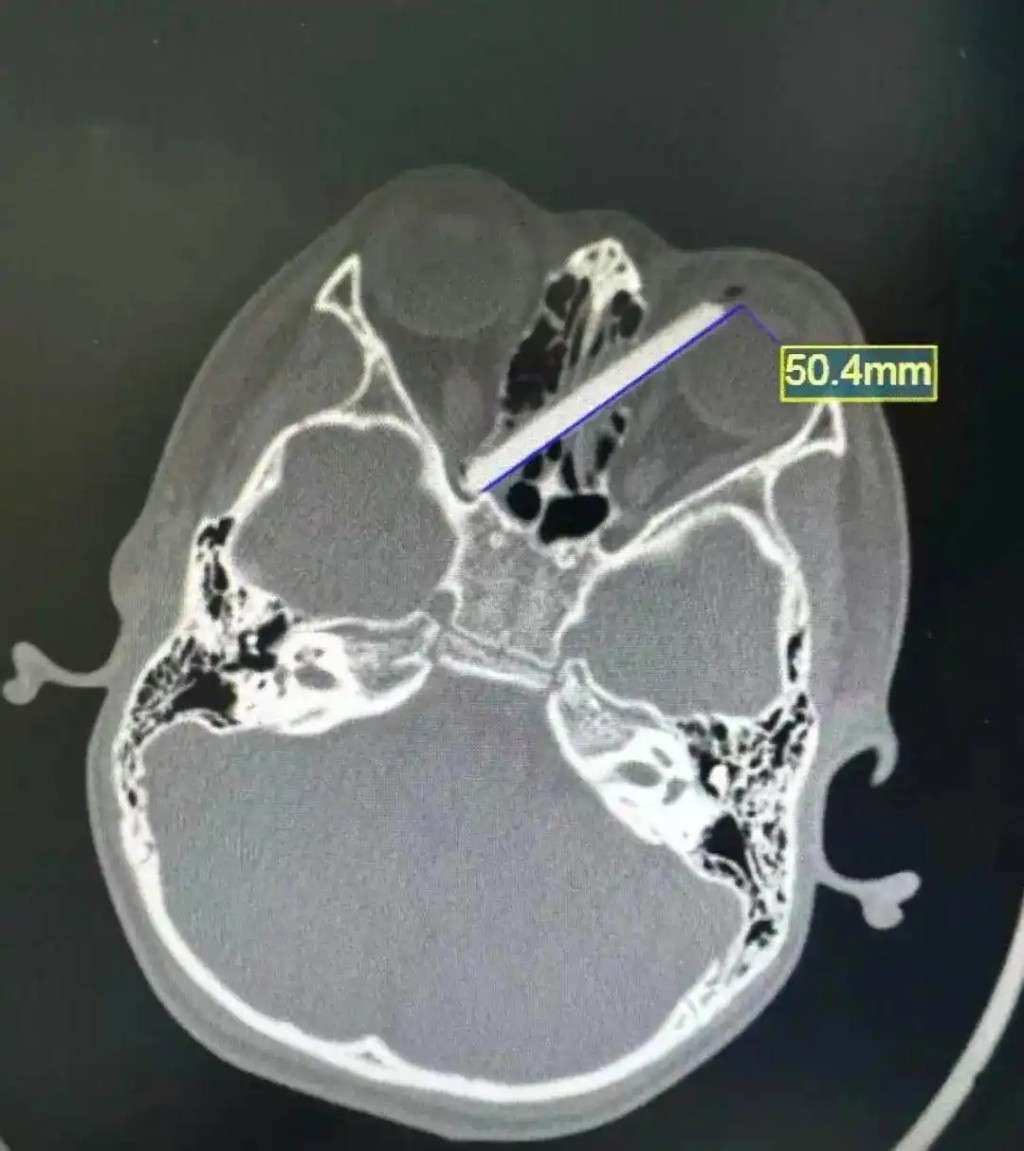

男童家長心急如焚地表示,事發時孩子拿著筷子準備開飯,突然摔了一跤,手中的筷子便少了一截,他們遍尋不獲,猜測斷筷已插入兒子眼中。經電腦掃描(CT)檢查後,證實了家長的猜測。影像顯示,該截5厘米長的斷筷,由左眼球壁插入,橫向貫穿雙側鼻竇,其尖端更深嵌至右眼的視神經管附近。

7歲童吃飯跌倒,5厘米斷筷插眼,橫貫雙側鼻竇。